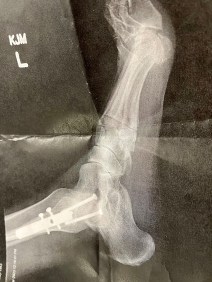

In fact, I registered for the 2023 race and I was meeting up with fellow blogger Jenny and her hubby. But several days before the race, I fell and broke my foot.

Not necessarily the hot weather as I knew how that would affect me but my FEET.

My neuroma bared its ugly head for the first time in 5 years. Then a blister formed on the other foot. When things were going from bad to worse, the last 3 miles or so were running into crazy wind gusts.

- My foot pain!!!!